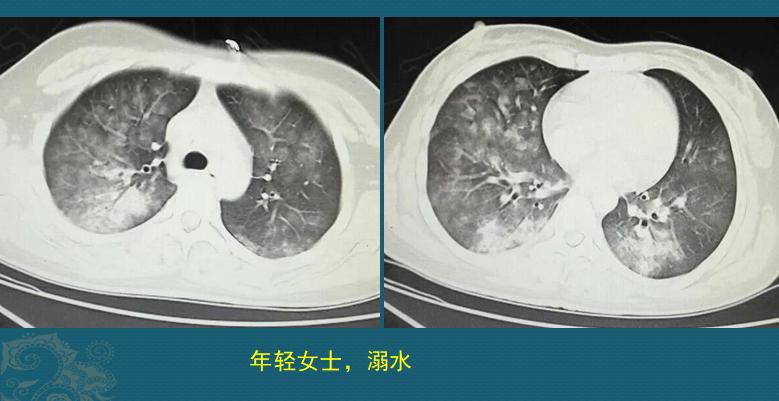

这是一位26岁女士,在人工湖游泳时溺水昏迷,呼吸、心跳停止,幸好被救生员及时发现,马上进行心肺复苏,呼吸心跳恢复,尽快送到医院,急诊CT发现双肺多发磨玻璃影,沿气道分布,部分肺实变(约溺水后2小时):

这是溺水性肺水CT肿的典型表现,形成原因主要是肺水肿和肺泡损伤:

1.淡水入肺,引起肺泡上皮肿胀;

2.吸入的大量水分冲洗肺泡表面活性物质(维持肺泡稳定的物质),使肺泡稳定性被破坏;

3.肺部毛细血管通透性增加、肺水肿;

4.大量水分入血增加血容量,加重心脏负担甚至引发急性心功能不全;如果是吸入污水,还可发生肺部感染。